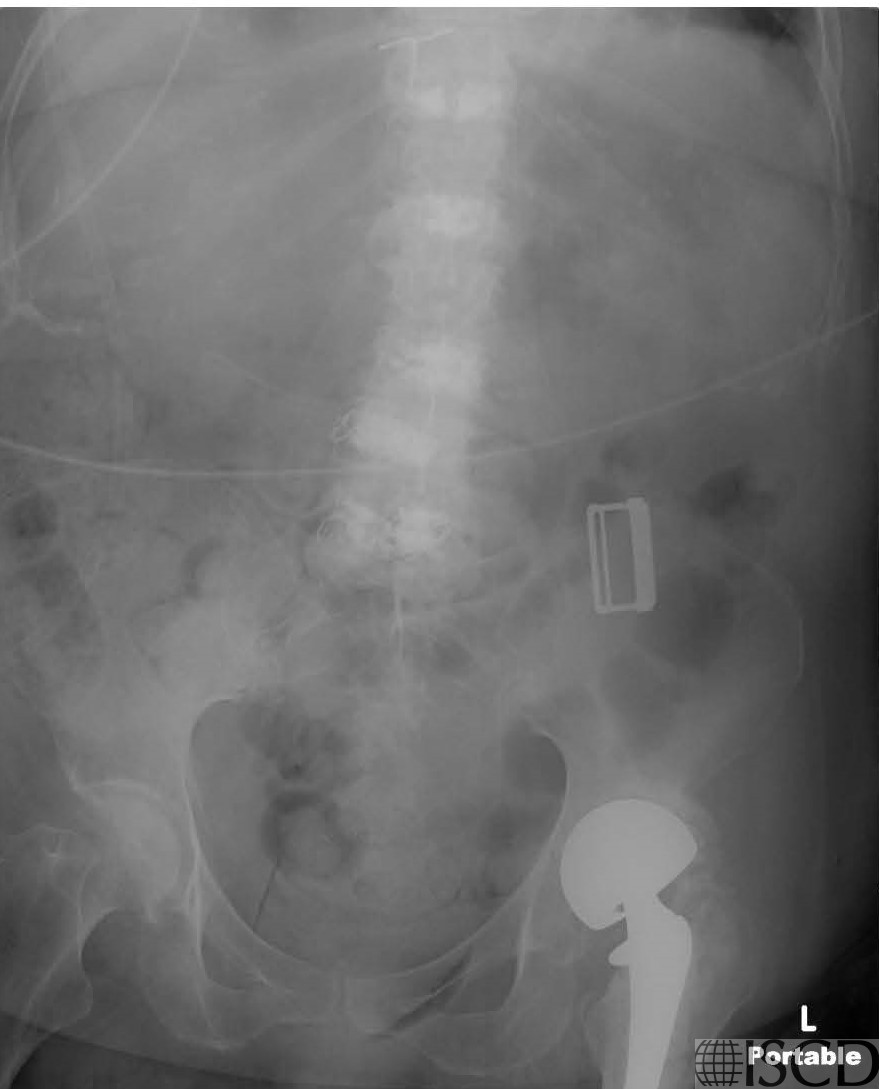

The accompanying radiograph whos the vertebral augmentation. A left total hip replacement and external buckle is also seen on the radigoraph

These images show vertebral augmentation in the lumbar spine.